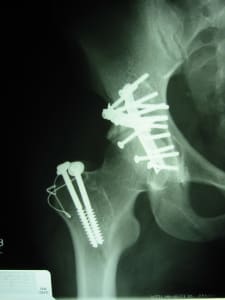

We spent a lot of time with 68 year old “Sissy” who was also a patient of mine in 2002 after a van backed into her as she sat on a wall and broke both her femur and tibia. I had to rod her femur without imaging in the OR and, as a consequence of flying blind, had to supplement her rod fixation with an improvised augment. Her x-ray shows something no one has seen before or since! She makes the most unbelievable roasty, toasty coconut oil by hand with nuts that she drags from her mountain side stash. It takes her all day to make 8 750ml bottles of oil. Great for cooking and just look at her skin!